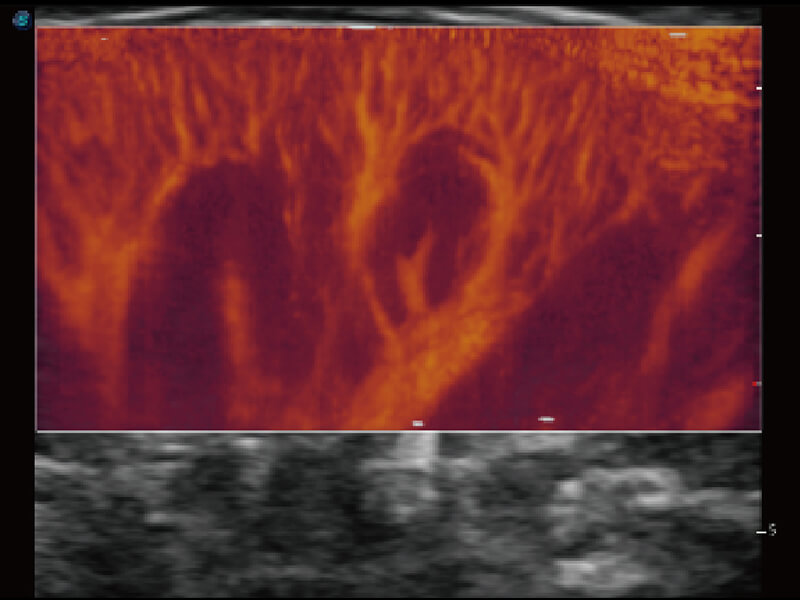

性能优异的硬件架构,极大提升超声系统的运行效率和数据处理能力。相比以往超声成像系统,Wis+平台为您带来极快的响应速度和成像帧频,提升检查流畅度。

S60探头工艺,从前端信号处理每一个环节采集无损声学数据,真实还原组织原貌,再现解剖细节。